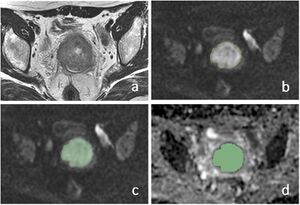

Publication: BMC Cancer. 2019 Nov 15;19(1):1115. PMID: 31729974 | PDF Authors: Zhao B, Cao K, Li XT, Zhu HT, Sun YS. Institution: Department of Radiology, Key Laboratory of Carcinogenesis and Translational Research, Ministry of Education, Peking University Cancer Hospital and Institute, Beijing, China. Abstract: BACKGROUND: The aim was to investigate the prognostic value of MR apparent diffusion coefficients (ADC) using histogram analysis (HA) in predicting disease-free survival (DFS) of cervical cancer after chemo-radiation therapy. METHODS: We retrospectively analyzed 103 women with pathologically proven squamous cell uterine cancer who received chemo-radiation therapy between 2009 and 2013. All patients were followed up for more than 2 years. Pre-treatment MR images were retrieved and imported for HA using an in-house developed software program based on 3D Slicer. Regions of interest of whole tumors were drawn manually on DWI with reference to T2WI. HA features (mean, max, min, 50, 10, 90%, kurtosis, and skewness) were extracted from apparent diffusion coefficient (ADC) maps and compared between the recurrence and non-recurrence groups after the 2-year follow-up. Univariate and multivariate Cox regression analysis was used to correlate ADC HA features and relevant clinical variables (age, grade, maximal diameter of tumor, FIGO stage, SCC-Ag) with DFS. RESULTS: One hundred three patients with stage IB-IV cervical cancers were followed up for 2.0-94.6 months (median 48.9 months). Twenty patients developed recurrence within 2 years. In the recurrence group, the min (P = 0.001) and 10% (P = 0.048) ADC values were significantly lower than those of the non-recurrence group. Univariate and multivariate Cox regression analysis revealed that ADCmin (P = 0.006, HR = 0.110) was significantly correlated with DFS. CONCLUSION: Pre-treatment volumetric ADCmin in histogram analysis is an independent factor that is correlated with DFS in cervical cancer patients treated with chemo-radiation therapy. |

Manual segmentation of ROIs in cervical lesion and schematic diagram of parameters. a–c Referring to T2WI and DWI, ROIs were drawn manually slice by slice on DWI images along the edge of the lesions in order to cover as much tumor area as possible without excluding cystic or necrotic areas. d The same ROIs were registered to ADC maps. |